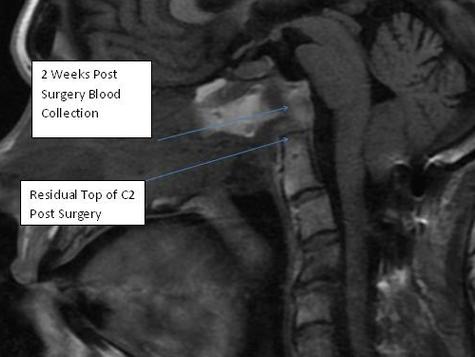

Physicians at UPMC in Pittsburgh developed new technique around 2010. Using a small endoscope, through the nose, then a small catheter through the back of the nasopharynx ( nose/mouth ) they removed ( via tiny drill ) most of C1 and C2. Quite risky being that close to brain stem. No small complications, sort of an all or nothing thing. This is me 2 weeks post surgery.

MRI 3 months post surgery -   Blood resolved. Brain stem relaxed and expanded forward by almost 4 mm which might as well be a football field (in places) in the brain for those who are not familiar with brain anatomy.